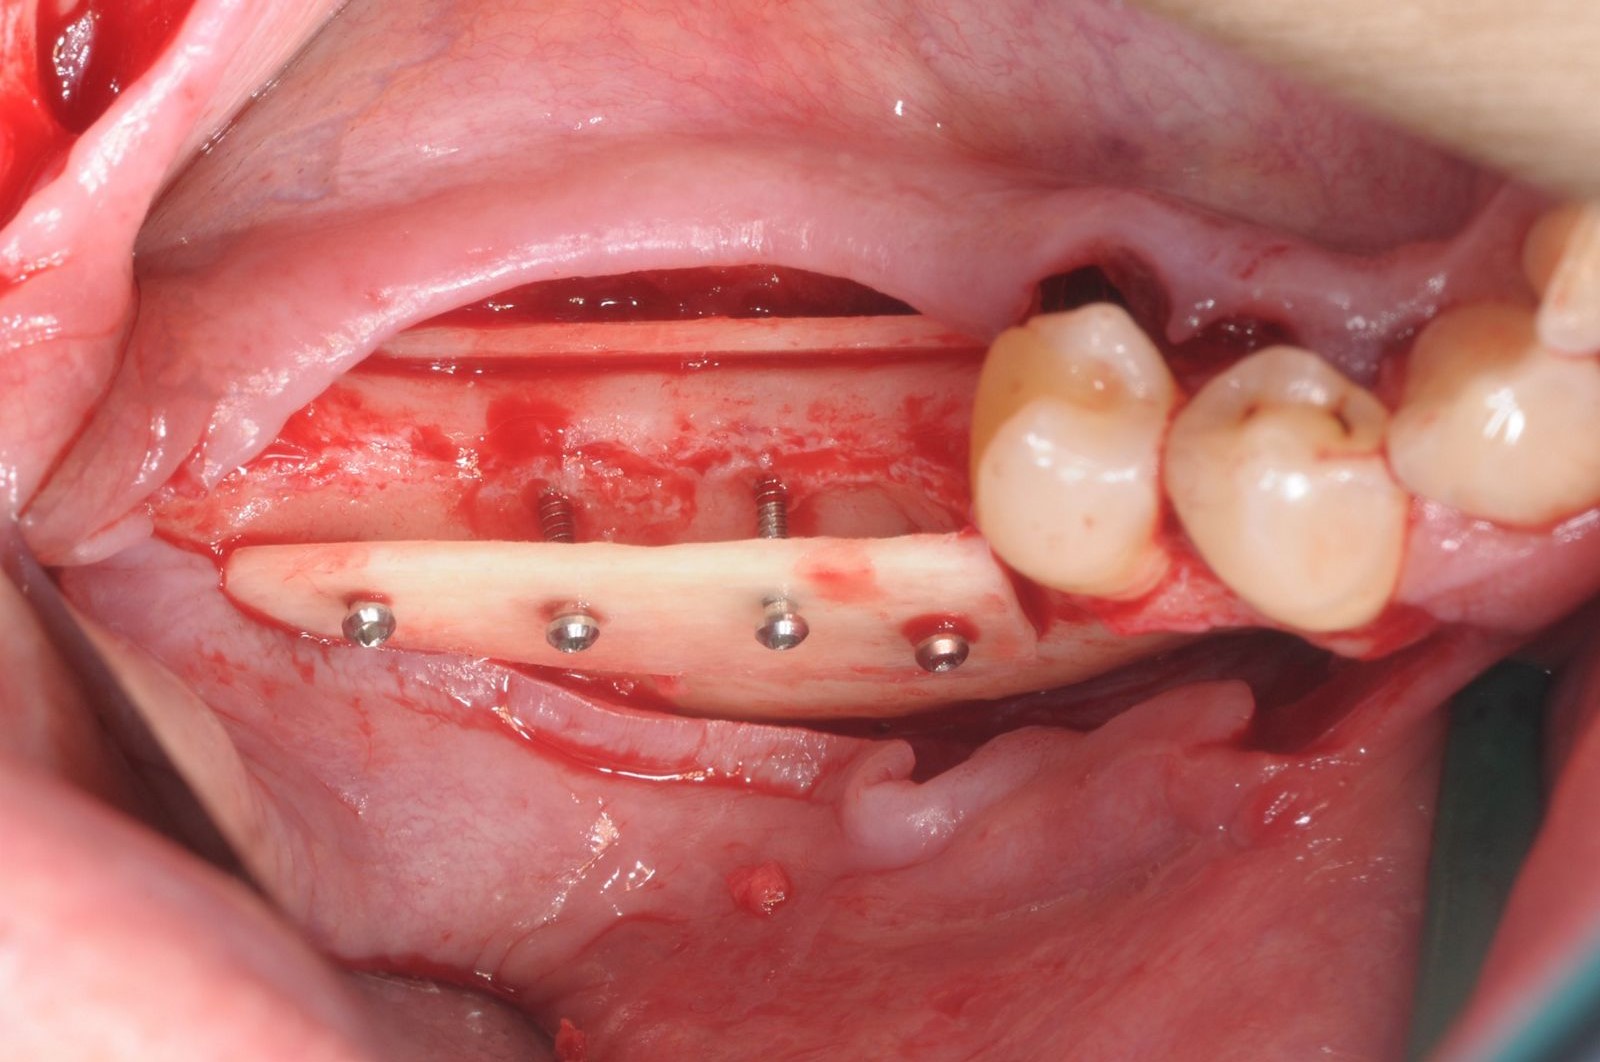

06/28 - Fixation of two defect-adapted maxgraft® cortico plates with osteosynthesis screwsThree-dimensional augmentation with maxgraft® cortico - Dr. R. Würdinger